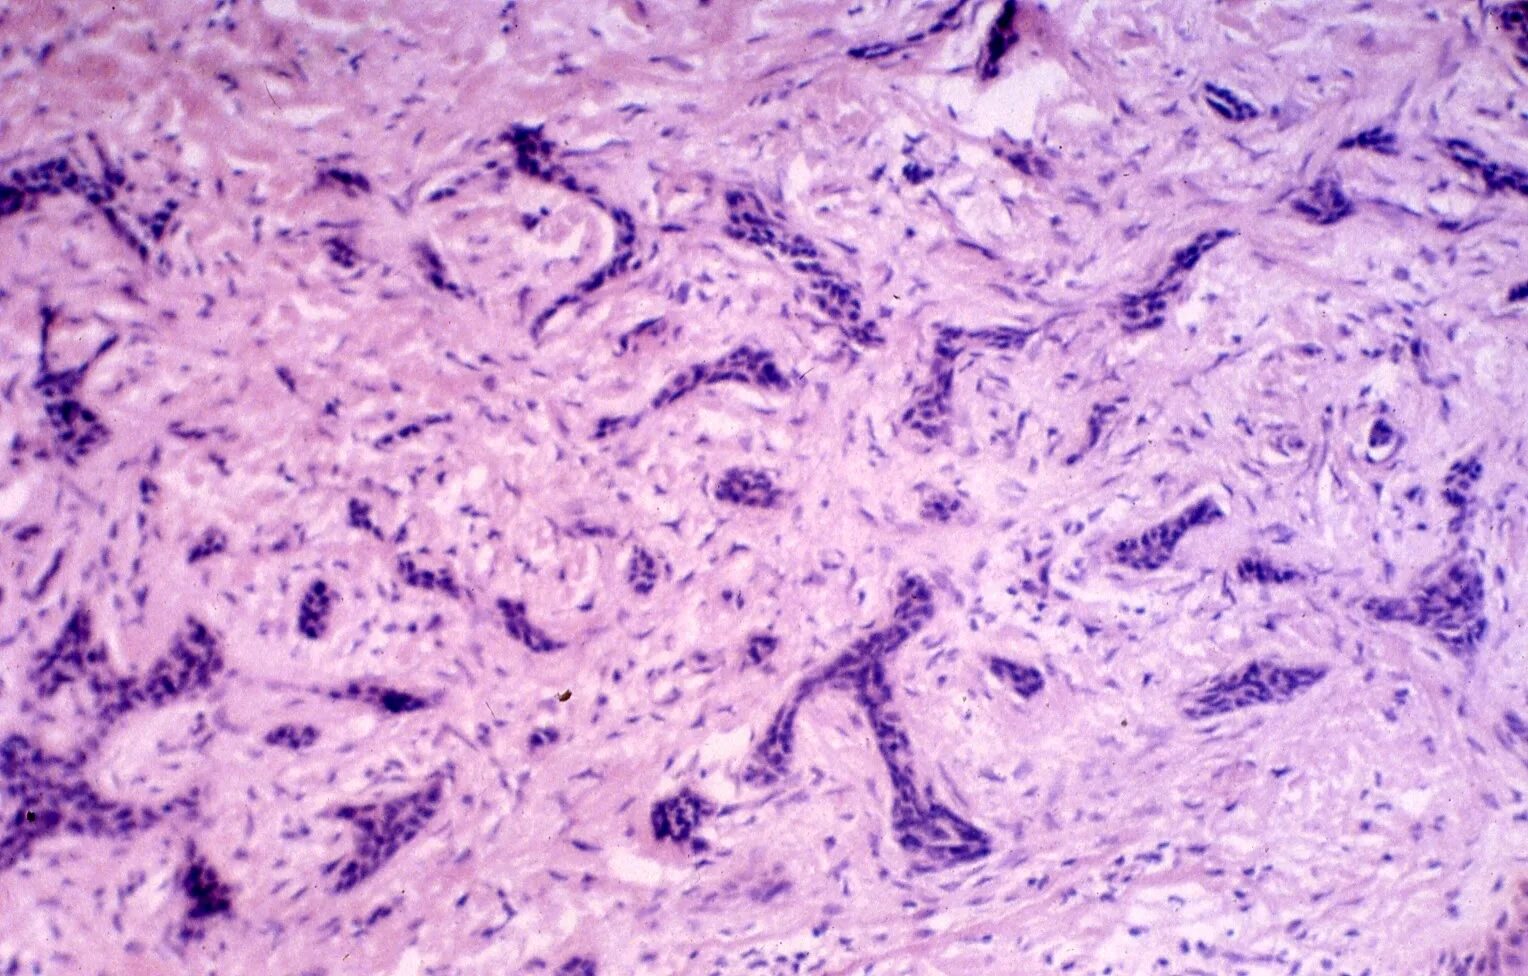

Что показала гистология замершей